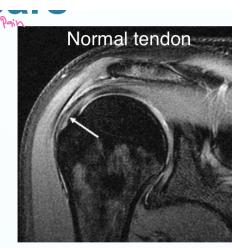

| Feel | • Temperature: Compare both sides (proximal to distal) and comment if symmetrical. • Tenderness: Palpate for tenderness (always compare to the left shoulder) starting at: • Sterno-clavicular (SC) joint • Clavicle • Acromio-clavicular (AC) joint • Greater Tuberosity (GT) & Biceps tendon • Scapular spine • Palpate and compare rotator cuffs (supraspinatus, infraspinatus) and deltoids. General: Tenderness (Generalized/specific), Temperature (compare distal/proximal, Rt/Lt). Anatomic: Skin, Subcut., Muscle (tone, bulk, twitches, gaps, tenderness), Bone (tenderness, mass, crepitus, landmarks: Sternoclavicular, Acromioclavicular, Coracoid Process, Greater Tuberosity, scapular spine, and scapula), Joint (swelling, effusion, crepitation, synovial thickening, joint line tenderness). Specific areas: Acromio-clavicular Jt., Bicipital groove. | ![]() |

| Special Tests | Rotator Cuff Power (compare both sides): • Instability (Bankart): Apprehension Test (abduct and externally rotate arm, apply anterior pressure, watch patient’s face). • Supraspinatus (Empty Can Test): Flex shoulder to 30° with thumbs down; ask patient to resist. • Impingement tests: Neer’s Impingement Test, Hawkins’ Impingement Test. or neer’s rotator cuff + abduction resistance for supraspinatus • Infraspinatus: Ask patient to perform external rotation against resistance (elbows at 90°). • Subscapularis: Ask patient to perform internal rotation against resistance OR use the Lift-Off Test. • Teres Minor: Ask patient to perform external rotation against resistance in 90° of shoulder abduction. • Biceps Tendon: Speed’s Test (resisted shoulder flexion with elbow extended and supinated) OR Yergason Test. • Deltoid: Axillary nerve assessment: Motor (active abduction - then drop test- Deltoid), Sensory (upper lateral aspect of arm). Serratus Anterior - Scapular Winging; long thoracic nerve: push against wall - observe back • AC Joint: Cross Body Adduction Test. • Muscle power tests: Abductors/Adductors, Internal/External Rotators, Serratus Anterior (winging), Biceps Brachii. | Apprehension test: Neer’s Impingement Test: Yergason Test: External / Internal Rotators Strength Test: Supraspinatus Test: Serratus Anterior - Scapular Winging; long thoracic nerve: Biceps Tendon & Ruptured long head: ![]() |